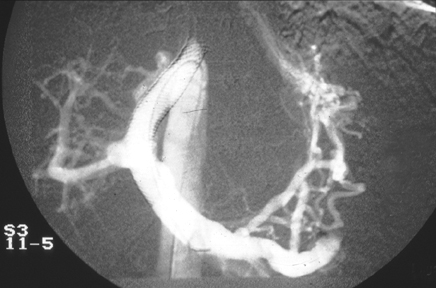

| The hepatic venogram views above and below reveal a transjugular intrahepatic portosystemic shunt (TIPS shunt) that extends from the hepatic venous outflow into the portal venous system in a patient with thrombosis from the Budd-Chiari syndrome. The shunt is blocked by thrombus, with no outflow. |